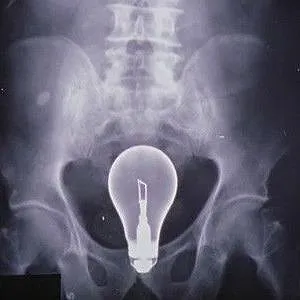

Molly travaille sur la résolution des conflits en milieu hospitalier et choisit le docteur Cox comme sujet d'étude. Pourvue de bonnes intentions, elle tente de réconcilier JD et Elliot, en compétition pour décrocher le poste de Chef des internes. Pendant ce temps, Cox, JD et le concierge essaient de résoudre le mystère de l'hôpital : comment extraire une ampoule du ventre d'un patient sans la briser ?